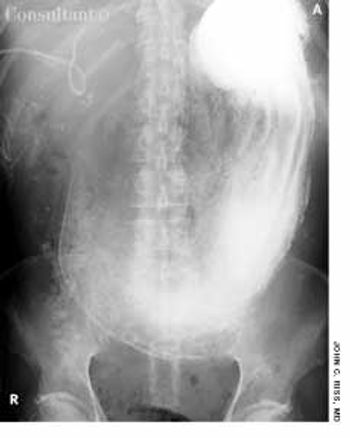

For 2 weeks, a 60-year-old man had severe nausea and vomiting. Two years earlier, he had had a cholangiocarcinoma, which was treated with palliative cholecystectomy followed by a course of rebeccamycin, an investigational chemotherapeutic agent.